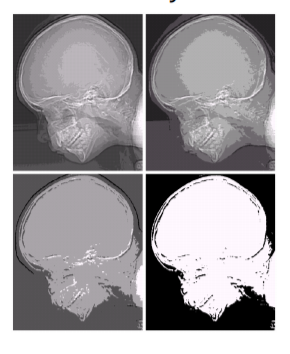

아래의 사진을 한 번 살펴보자. 이 사진은 Intensity level이 각각 16, 8, 4, 2인 경우를 나타낸다. 살펴보다 보면, 첫 번째 사진처럼 Intensity가 가장 클 때 정교하게 표현되는 것을 확인할 수 있다.